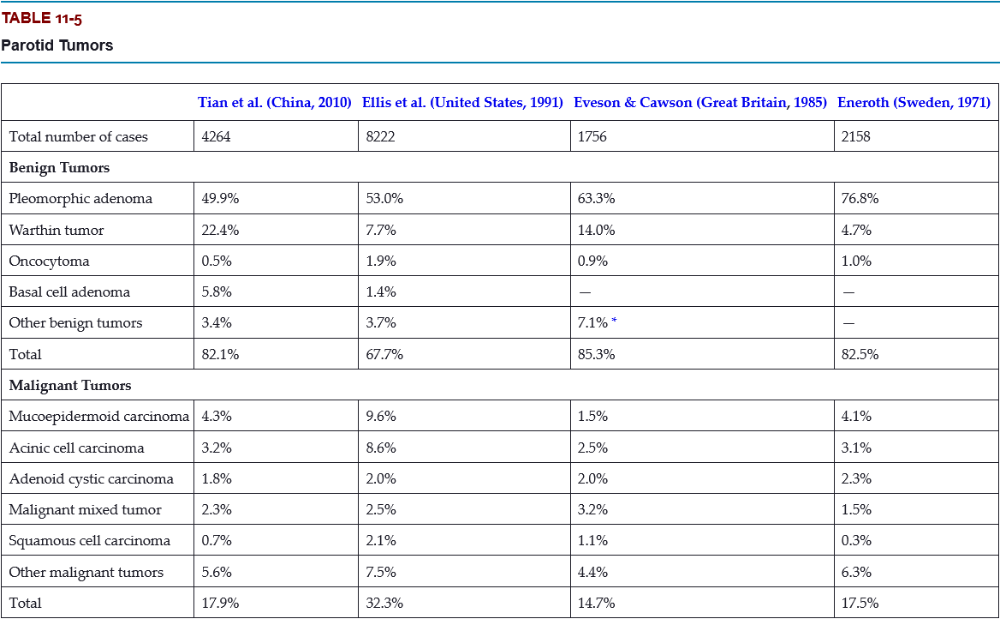

What is the most common type of parotid gland tumor?

- Warthin tumor

- mucoepidermoid carcinoma

- pleomorphic adenoma

- acinic cell carcinoma

C. pleomorphic adenoma

The pleomorphic adenoma is overwhelmingly the most common tumor, representing 50% to 77% of all cases in the parotid gland. Warthin tumors are also fairly common, accounting for 5% to 22% of cases.

What is the most common malignant tumor of the submandibular gland?

- mucoepidermoid carcinoma

- acinic cell carcinoma

- adenoid cystic carcinoma

- squamous cell carcinoma

D. adenoid cystic carcinoma

Only 8% to 11% of salivary tumors occur in the submandibular gland, but frequency of malignancy is much greater than for the parotid, ranging from 26% to 45%.

What is the most likely site for a malignant salivary gland tumor?

- parotid gland

- submandibular gland

- sublingual gland

- minor glands

C. sublingual gland

Tumors of the sublingual gland are rare, comprising no more than 1% of all salivary neoplasms. However, 70% to 95% of sublingual tumors are malignant.